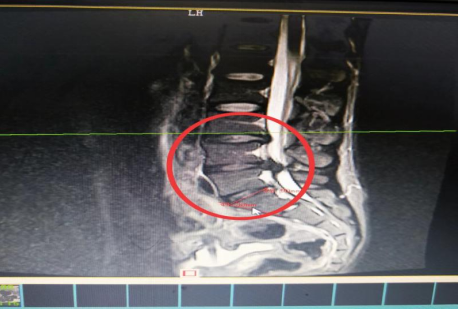

10分鐘后,患者肖先生在沒(méi)有家屬陪同的情況下被緊急送到骨科一區(qū)病房。接診滿(mǎn)頭大汗、非常緊張的肖先生,舒小林醫(yī)師仔細(xì)詢(xún)問(wèn)了病情。原來(lái)肖先生從事搬運(yùn)行業(yè),半年前就因腰腿痛就醫(yī),當(dāng)時(shí)在保守治療后稍有緩解,并沒(méi)有引起重視。直到11月13日下午因搬重物后突然感到腰腿劇烈疼痛、麻木、大小便困難,這才撥打了120急救電話(huà)。骨科一區(qū)錢(qián)軍副主任、舒小林醫(yī)師立即給患者作了詳細(xì)的體查,并立即聯(lián)系做急診腰椎磁共振確定有無(wú)神經(jīng)受壓。腰椎磁共振結(jié)果提示:腰4/腰5椎間盤(pán)膨出,導(dǎo)致馬尾神經(jīng)嚴(yán)重受壓,有明顯的手術(shù)指征,如不盡快手術(shù)會(huì)致神經(jīng)受損難以恢復(fù)。錢(qián)軍副主任來(lái)到肖先生病床前,將手術(shù)方案、手術(shù)風(fēng)險(xiǎn)及并發(fā)癥詳細(xì)告知肖先生本人,肖先生表示同意并簽字馬上手術(shù)。